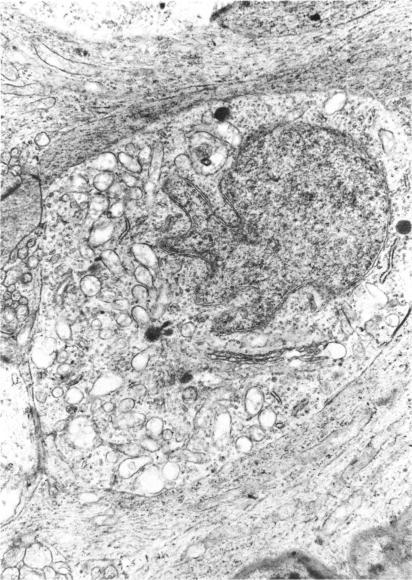

Three major pathologic processes caused by light in the primate retina: a search for mechanisms.

Trans Am Ophthalmol Soc. 1982;80:517-79.